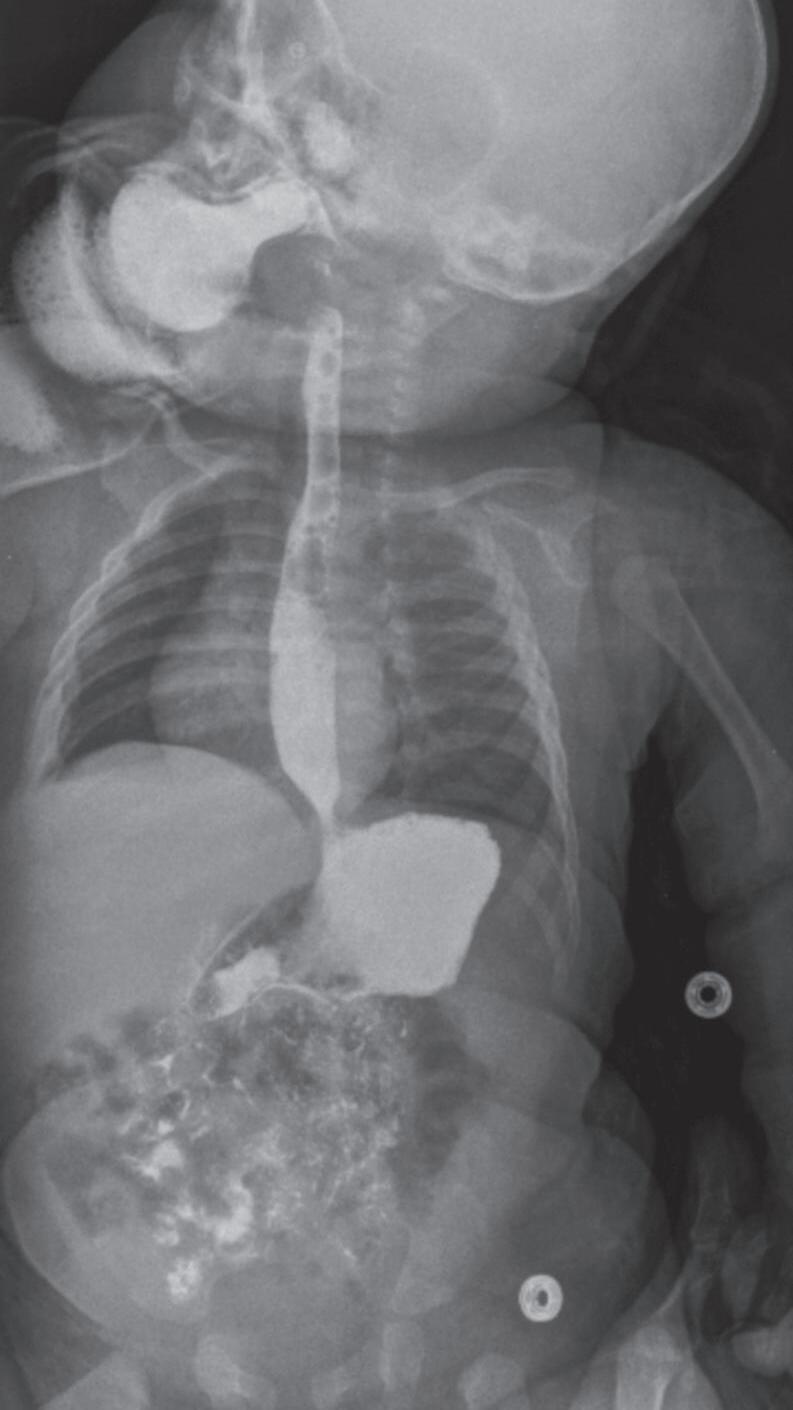

Fig. 1-1. Montagem de duas imagens radiográficas em visão anteroposterior demonstrando o percurso da deglutição desde a cavidade oral até o estômago (a) no adulto e (b) no bebê.

Fig. 1-2. Demonstração das estruturas envolvidas no processo da deglutição nas visões (a) lateral e (b) anteroposterior na imagem radiográfica.